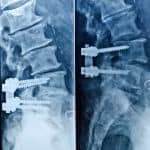

- Artrodese lombar

- Artrodese torácica

- Artrodese cervical anterior

- Artrodese cervical posterior

- Artrodese occipto-cervical

- ALIF, OLIF, TLIF